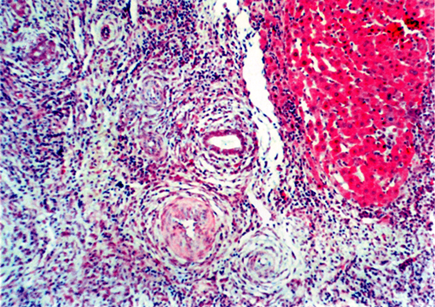

我们实验室以DA大鼠为供体,BN大鼠为受体进行原位肝移植,术后1~30天连续皮下注射环孢素A(lmg/kg/d),成功建立了大鼠肝移植慢性排斥反应模型。慢性排斥反应在术后30到60天内产生,中位生存期为58±14.93天。术后两个月病理学检查提示,移植物中有明显的淋巴细胞、中性粒细胞与嗜酸性粒细胞等炎性细胞浸润,同时胆管增生与胆道损伤情况也比较明显,胆管上皮局灶性坏死超过50%,一些胆管完全消失或纤维化。肝结构从肝小叶结构变化为大部分由结节与纤维组成的组织结构。残余肝细胞表现为退行性病变与坏死,连接汇管区出现完全与不完全纤维隔板。动脉管壁可见不同程度的纤维细胞与炎性细胞沉积,血管闭塞范围超过50%,一些动脉被完全阻断或纤维化(图4-2)。

图4-2 A

图4-2 A:DA-BN大鼠肝移植(皮下注射环孢素A lmg/kg/d×30天)术后60天,图示泡沫细胞阻塞性动脉病变,胆管明显减少甚至消失。B:DA-BN大鼠肝移植(皮下注射环孢素A lmg/kg/d×30天)术后60天,图示肝正常结构大量破坏,代之一纤维化组织和炎症,胆管减少,右上角显示正在纤维化消失的胆管(H&E染色,×100)